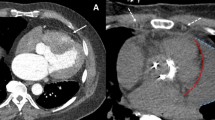

In this experiment, we showed good success using “passive” commercial CMR needles that are visualized based on intrinsic materials properties. In other work, we have shown superior visibility using an investigational “active” antenna-needle (Figure 4) [17]. Both may enable more sophisticated non-surgical treatments for structural heart disease, including direct transthoracic implantation of large appliances into the heart [16].

Comparison of “passive” versus “active” visualization of needles during CMR guided pericardial access. The “passive” titanium needle (panel A, black artifact indicated with white arrows) is compared with an “active” antenna needle (panel B, green colorized signal indicated with white arrow). The active needle is more conspicuous. This demonstration uses a lateral access approach and no pericardial effusion.